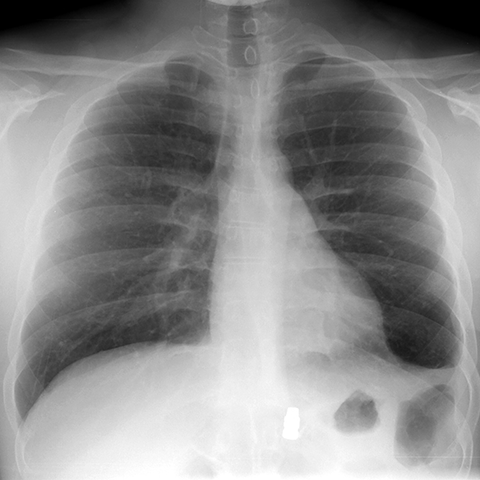

PA Chest Radiograph with Bullet [1 of 2]